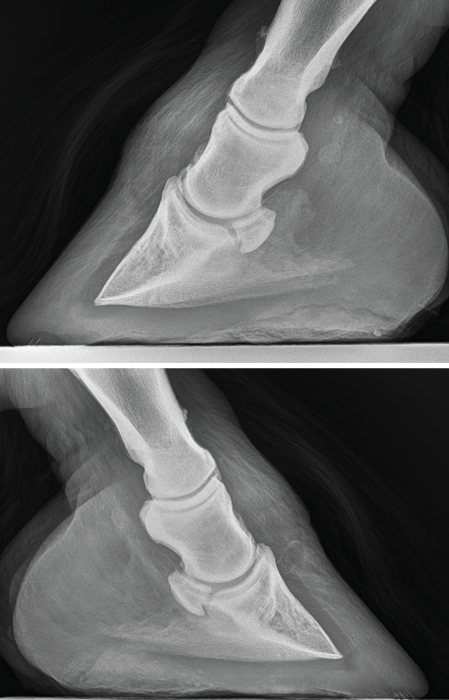

While Jackson’s sidebone remains unchanged, radiographs show early navicular remodeling in the right front and arthritic changes in the lower half of both front pasterns. Source: Esco Buff

Radiographic Revelations

In mid-July, radiographs confirmed unchanged sidebone progression but revealed early navicular remodeling in the right front and arthritic changes in both front pasterns.

These changes are occurring in the lower half of the second phalanx (P2 or short pastern bone), affecting both articular (in the joint) and non-articular surfaces — classic ringbone.

This shifts my priorities. My focus now is on improving enrollment and easing caudal hoof loading, especially in the right front. The veterinarian and I agreed to monitor with quarterly imaging.